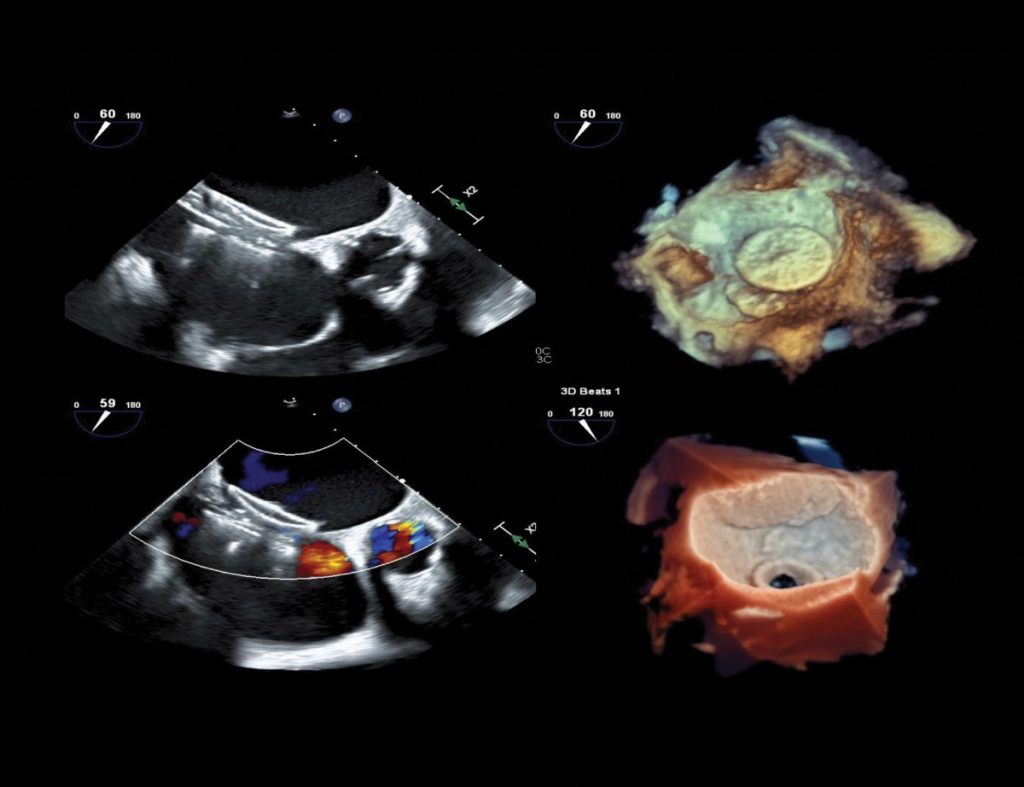

- Echocardiography-led structural heart imaging

- Our TEE team supports structural interventions across all major innovative clinical trials.

- 3D TEE, intracardiac echo (ICE), strain imaging, CFQ, and real-time fusion imaging (TEE or CT + fluoro) are part of our daily practice in structural and interventional cases.